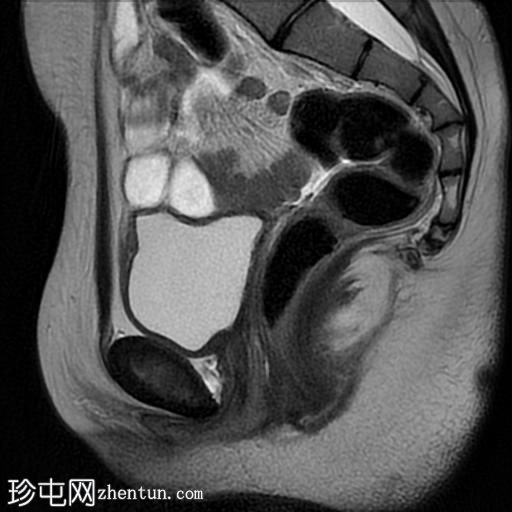

轴位

T1加权像

轴位T1加权像

脂肪抑制序列显示:

女性外生殖器

子宫、宫颈、阴道上2/3及卵巢缺失

双侧睾丸异位,沿腹股沟管清晰可见

MRI表现符合伴女性外生殖器的雄激素不敏感综合征(男性假两性畸形)。